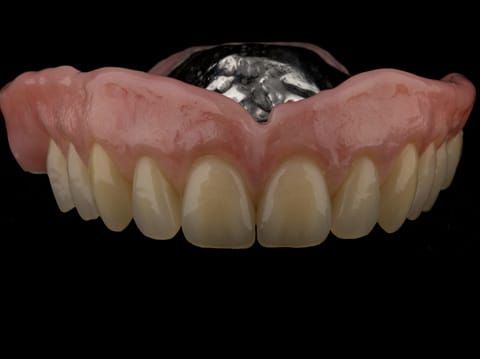

- Cobalt chromium reinforced gasket denture - using a Molloplast B "O" ring to retain and stabilise the denture. This was my professional preference as this was the least invasive and simplest solution to this dental problem. Should the UR7 require removal in the future - an artificial tooth could be added - resulting in a complete denture. The patient would have adapted to the denture fully by this stage and have good neuromuscular control of the prosthesis.

Following consultation and second discussion appointment the patient chose to have option 2 namely, a window denture - maxillary cobalt chromium based partial denture. The clinical situation and treatment process is shown in detail below with photographs. The patient was successfully rehabilitated with this and her quality of life considerably improved. The clinical work was provided by Finlay and the technical work by Rowan.